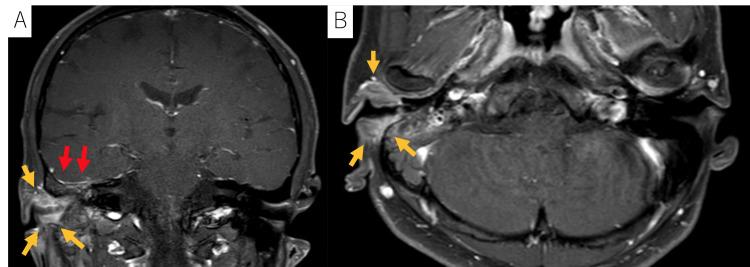

一名45岁男性,有抗NMDAR脑炎病史,表现为累及整个外耳道的右侧EACC。他的主诉是右侧耳漏。患者没有免疫功能低下。组织病理学分析证实了中度分化鳞状细胞癌的诊断(图3)。MRI显示右中颅窝硬脑膜增强,表明肿瘤浸润(图4A、4B)。根据改良的匹兹堡分类法,该疾病被归类为T4。没有证据表明颈部淋巴结受累或远处转移。患者接受了根治性同步放化疗,IMRT(70 Gy/35 Fr)联合顺铂(100 mg/m2,三个三周疗程)。

治疗后两个月,患者被送往急诊室,主要症状是意识受损。CT扫描显示右颞叶有一个低密度区域的环状增强病变,与最大直径为36毫米的颞叶脓肿一致(图5A)。立即开始引流和抗生素治疗。脓肿和耳漏中均发现解脲弯曲杆菌,表明感染起源于外耳道。根据细菌敏感性,美罗培南和利奈唑胺的初始抗生素治疗调整为头孢曲松和甲硝唑。尽管进行了抗生素治疗,脓肿仍然存在,并有持续的活动性感染迹象(图5B)。

图4 A、 B:MRI图像显示肿瘤(由黄色箭头表示)和右中颅窝硬脑膜增强(由红色箭头表示)。根据改良的匹兹堡分类法,该疾病被归类为T4。患者无颈部淋巴结受累或远处转移

图5 A: CT扫描显示右颞叶有一个低密度区域的环状强化病变,与颞叶脓肿一致,最大36毫米。脑脓肿在放疗后两个月形成。B:尽管进行了引流和抗生素治疗,脑脓肿仍然存在